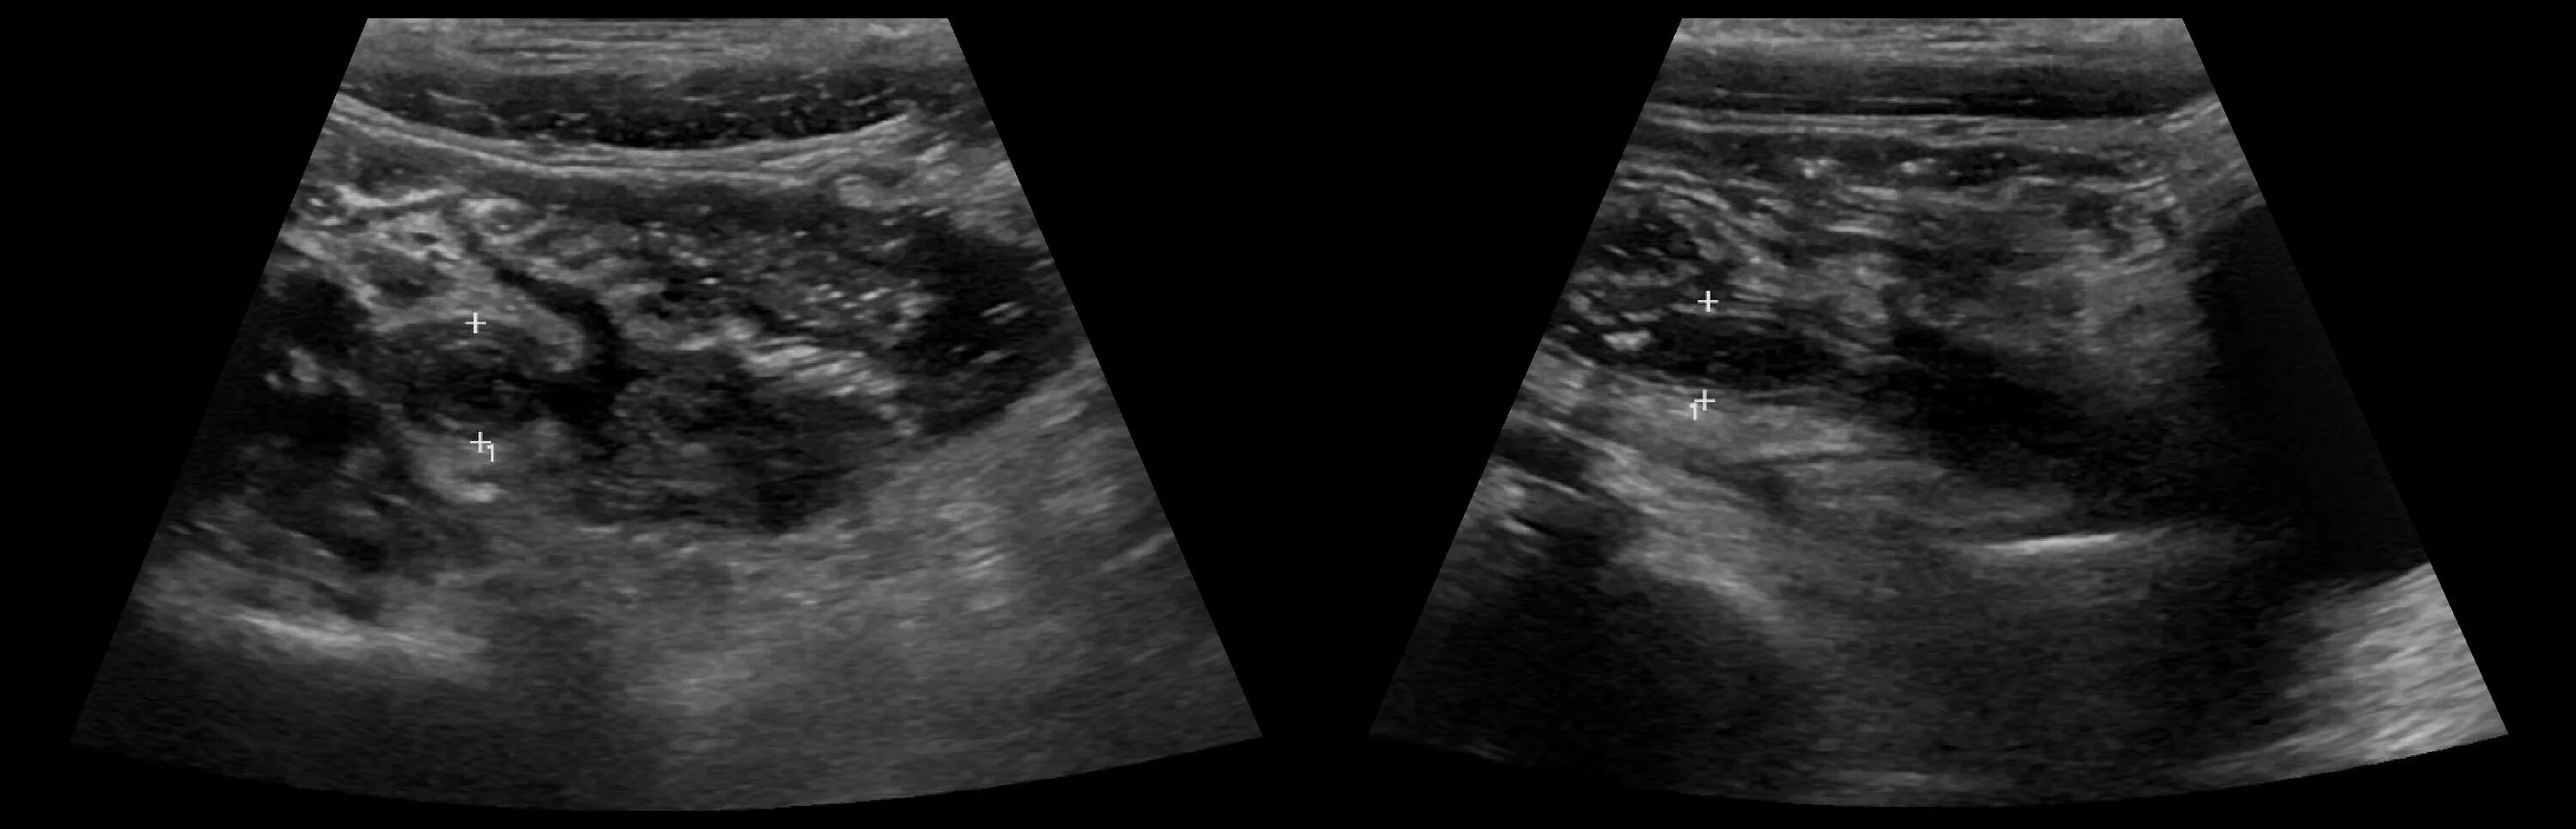

Аппендицит на узи можно ли